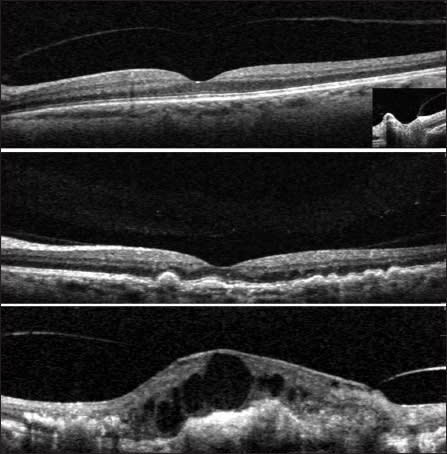

Figure 1. Classification scheme of hyaloid adhesion and vitreomacular traction (VMT) seen with SD-OCT. A normal eye of an elderly patient: The hyaloid membrane is visible and completely detached from the fovea, though there is a persistent adhesion to the optic nerve (top). Eye with nonexudative AMD and drusen (center): The hyaloid is attached over the entire macula, including the fovea. Eye with choroidal neovascularization (bottom). The persistence of hyaloid adhesion causes VMT over the CNV complex: A focal distortion of the retinal profile is visible at the site of hyaloid attachment. Reprinted from Am J Ophthlamol, vol. 146, Mojana F, Cheng L, Bartsch DU, et al., The role of abnormal vitreomacular adhesion in age-related macular degeneration: spectral optical coherence tomography and surgical results, pp. 218-227, Copyright 2008, with permission from Elsevier.